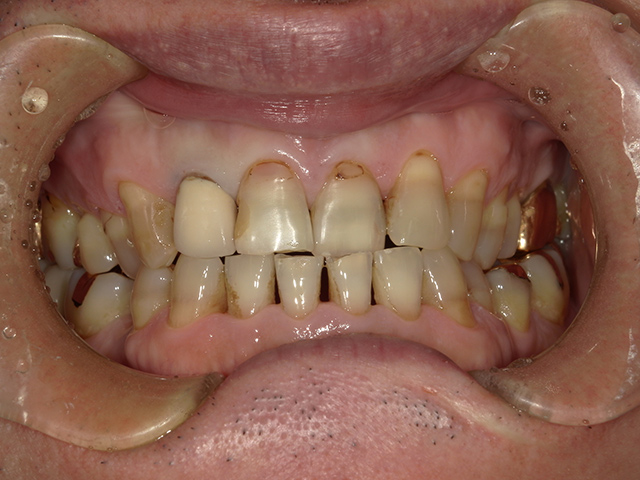

ダイレクトボンディングとは、高品質なレジン(樹脂)を直接歯に盛り付け、形や色を1本1本丁寧にデザインする審美修復治療です。

歯をほとんど削らない

従来のセラミック修復と比べ、削る量を最小限に抑えられます。(全く削らない症例もあります)

「できるだけ歯を削りたくない」「神経を残したい」という方に最適です。

すきっ歯・欠けた歯の修復に最適

そのため、症例によっては矯正治療やセラミック治療との併用をご提案することもあります。